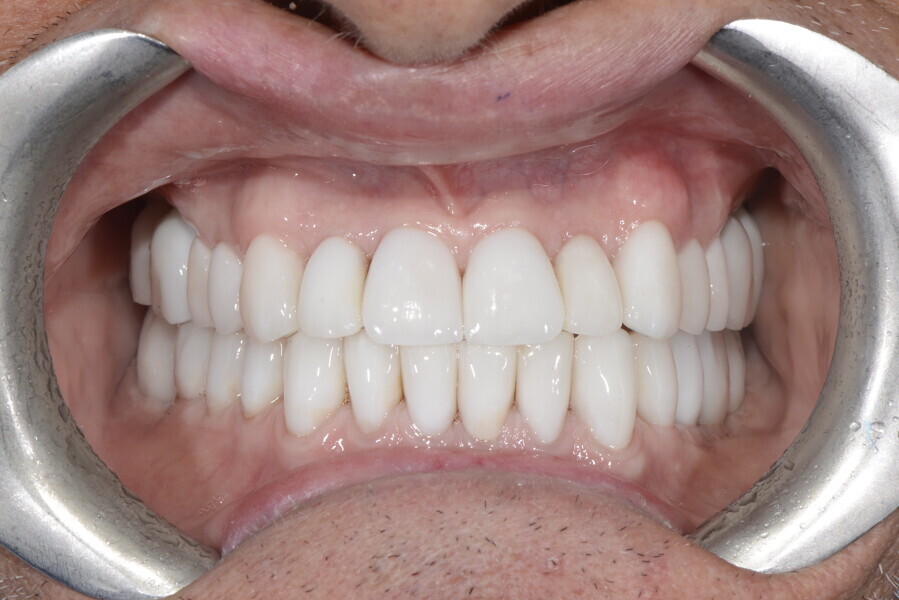

After the first phase of aligner treatment, we had achieved better inter-arch coherence, better maxillary arch expansion, and some space for improving the anterior tooth proportions restoratively (Fig. 19). We then temporarily restored the anterior teeth directly with composite, closing the spaces, improving the tooth proportions and further increasing the maxillary arch expansion (Fig. 20). We used restorative arch expansion to reduce the orthodontic destabilisation of the teeth to achieve the correct inter-arch coherence and retain the teeth in the cortical bone.38 A refinement aligner phase was undertaken to improve the final alignment of the gingival zenith and to improve the inter-arch coherence (Fig. 21). The periods of the first orthodontic phase and of the refinement were used to augment the mandibular and maxillary bone and to place the implants (Fig. 22). At the end of the orthodontic treatment, the case was finalised with ceramic veneers in the anterior area and temporary restorations on the implants in the posterior area (Figs. 23–26).

The provisional phase of about four months was important to allow the peri-implant tissue to mature and to teach the patient to chew correctly with chewing gum, cotton rolls and silicone masticatory sticks. This is fundamental training for the patient to achieve the correct alternating unilateral masticatory cycle needed to obtain the ideal rehabilitation of the masticatory system. We wanted the patient to achieve ideal masticatory and swallowing function. After sufficient rehabilitation time, we finalised the case with posterior zirconia crowns screwed on to the implants (Fig. 27).26

Our ideal final rehabilitation goals were:

• posterior stability;

• inter-arch coherence and U-shaped arches;

• anterior freedom during mastication;

• minimum disclusion vertical dimension;

• alternating unilateral masticatory cycle;

• physiological swallowing and high tongue posture against the palate; and

• mandibular disclusion advancing the mandible freely.

For maintenance purposes, after prosthetic finalisation, the patient was to carry on with the Froggymouth therapy and to use the Ri.P.A.Ra. for physiotherapeutic exercises and mastication training (Fig. 28). It was strongly recommended that the patient wear a mandibular occlusal splint during sleep. This occlusal splint was designed with disclusion guides to advance the mandible and ensure balanced contralateral support (Fig. 29).11, 39 We achieved an aesthetic appearance with adequate inter-arch coherence and a better cephalometric result (Figs. 30 & 31).